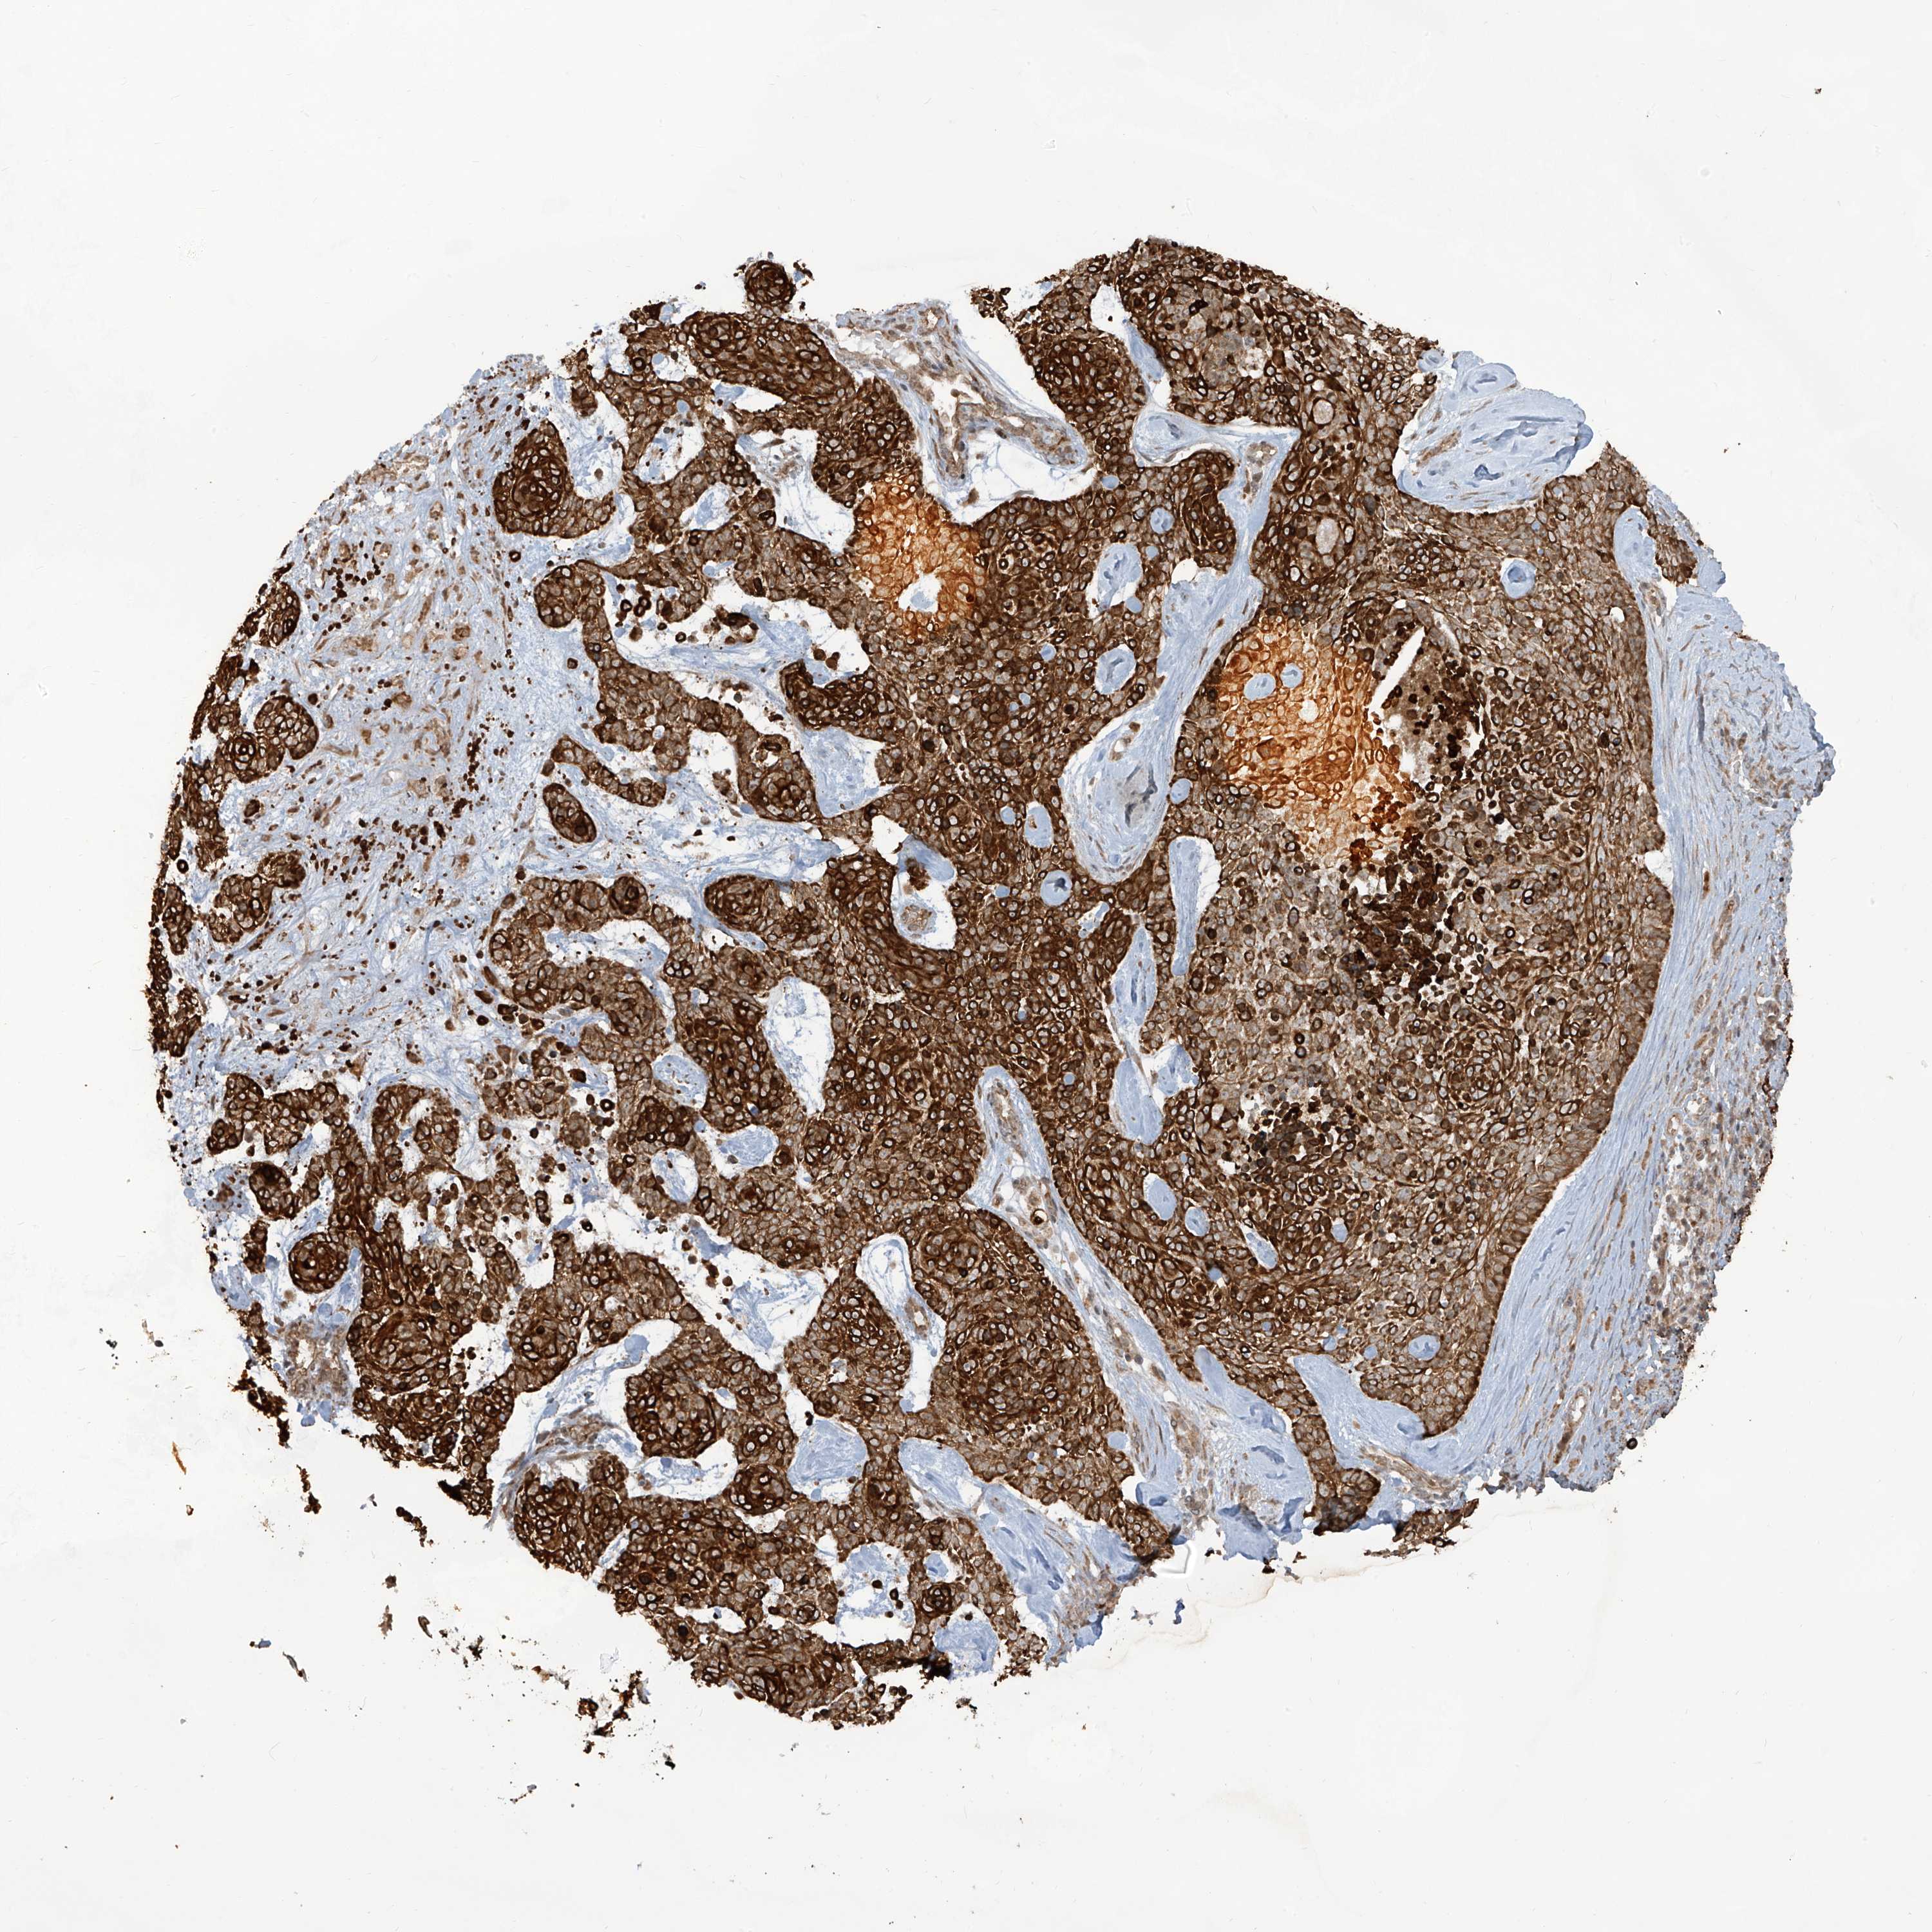

SKIN CANCER - Protein expressioni

A mouse-over function shows sample information and annotation data. Click on an image to view it in a full screen mode. Samples can be filtered based on level of antibody staining by selecting one or several of the following categories: high, medium, low and not detected. The assay and annotation is described here.

Antibody stainingi

Antibody staining in the annotated cell types in the current human tissue is reported as not detected, low, medium, or high, based on conventional immunohistochemistry profiling in selected tissues. This score is based on the combination of the staining intensity and fraction of stained cells.

Each image is clickable and will lead to virtual microscopy that enables deeper exploration of all samples and also displays staining intensity scores, fraction scores and subcellular localization as well as patient and tissue information for each sample.

Antibody HPA034776

Staining

High

Medium

Low

Not detected

Intensity

Strong

Moderate

Weak

Negative

Quantity

>75%

75%-25%

<25%

None

Location

Nuclear

Cytoplasmic/membranous

Cytoplasmic/membranous,nuclear

Basal cell carcinoma

Squamous cell carcinoma, NOS

Squamous cell carcinoma, metastatic, NOS